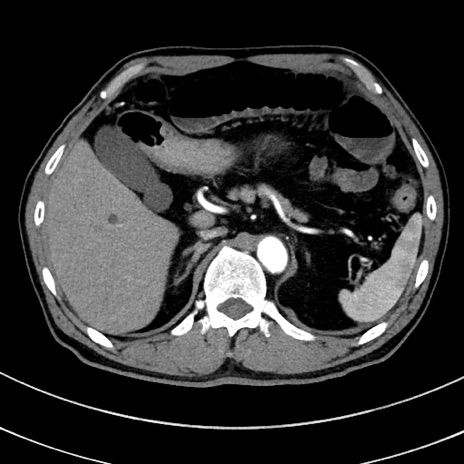

症例8(横断像)

【症例】 60歳代男性

【主訴】 黒色吐物

【現病歴】 4日前から嘔気自覚、2日前の朝食後にも嘔気あり、自分で手で嘔吐反射起こし嘔吐したところ血が混ざっていたため受診。

【既往歴】 5年前汎発性腹膜炎を伴う急性虫垂炎で手術、高血圧、前立腺肥大症、高脂血症

【身体所見】 腹部正中に手術癩痕あり 腹部平坦・軟圧痛なし膨満感あり

【データ】WBC 8400、CRP 4.54